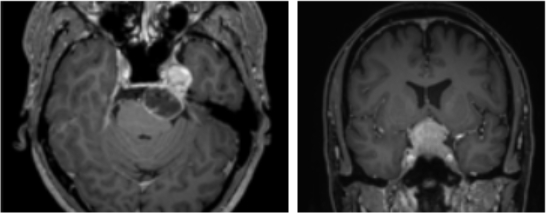

µÎ°³ÀúÁ¾¾çÀº µÎ°³°ñ ¹Ù´Ú¸é(µÎ°³Àú)°ú ¸¸³ª´Â ³ú ºÎÀ§¿¡ ¹ß»ýÇÏ´Â Á¾¾çÀÌ´Ù. ³ú ±í¼÷ÇÑ °÷¿¡ »ý±ä Á¾¾çÀ» Á¦°ÅÇØ¾ß Çϱ⠶§¹®¿¡ ¼ö¼úÀÌ ¸Å¿ì ±î´Ù·Ó´Ù. / »ï¼º¼¿ïº´¿ø Á¦°ø

¡°µÎ°³Àú¸¦ ÀÚ¼¼È÷ º¼ ¼ö ÀÖ´Â CT°Ë»ç°¡ ÇÊ¿äÇÏ´Ù. Á¾¾çÀÌ Ä§¹üÇÑ À§Ä¡¸¦ ÆÄ¾ÇÇϱâ À§ÇØ MRI °Ë»çµµ ½Ç½ÃÇÑ´Ù. Á¾¾çÀÌ ½Ã½Å°æÀ̳ª û½Å°æÀ» ¾Ð¹ÚÇϰí ÀÖÀ¸¸é ½Ã°¢ °Ë»ç, û°¢ °Ë»ç¿Í °°Àº ±â´É °Ë»ç¸¦ Çϰí, ¾ç¼º¡¤¾Ç¼º ¿©ºÎ ÆÇº°À» À§ÇÑ PET °Ë»ç ¶ÇÇÑ ÁøÇàÇÒ ¼ö ÀÖ´Ù. µÎ°³ÀúÁ¾¾ç ¼ö¼úÀº µÎ°³Àú¸¦ ÅëÇØ ³ú·Î ÇâÇÏ´Â ÁÖ¿ä Ç÷°üµéÀ» ¼Õ»ó½ÃŰÁö ¾Ê´Â °ÍÀÌ Áß¿äÇϱ⠶§¹®¿¡ µÎ°³ÀúÁ¾¾çÀÌ ¹ß°ßµÇ¸é ¿ì¼± ³úÇ÷°ü Á¶¿µ¼úÀ» ÅëÇØ Ç÷°üµéÀ» È®ÀÎÇÑ´Ù.¡±